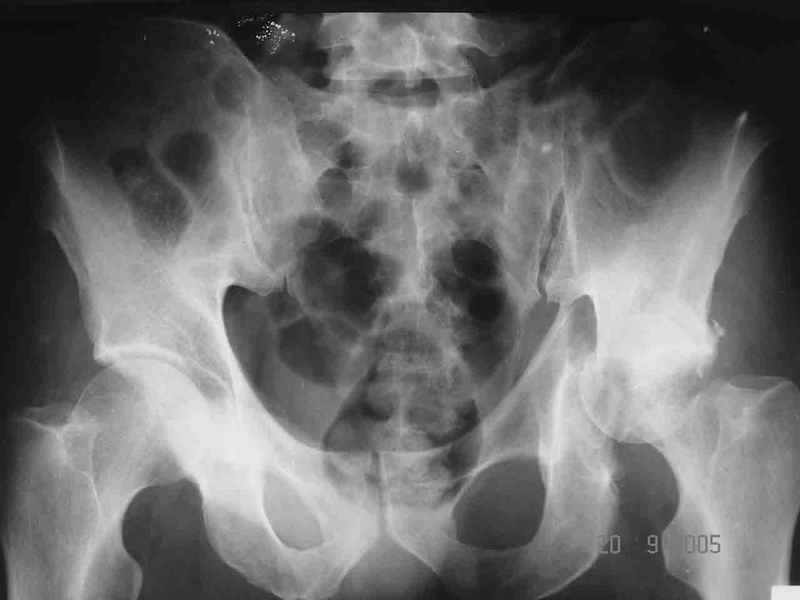

Привет! Вот недавно прооперировали похожий на ваш случай - впадина + шейка (правда у нас впадина поперечный+задний край). После травмы прошло 4 недели. мужчине 46 лет. С такой комбинацией все показания к первичному протезированию. Морально и технически мы к этому уже созрели.Но больной не собрал денег на протез. Выполнили остеосинтез впадины и шейки, прекрасно понимая, что головка вскоре рассосется, мы хотя бы надемся что к этому времени таз срастется, как говорится создали все условия для дальнейшего протезирования (может, и протез в последующем подешевле будет, в смысле, без укрепляющего кольца?). Привет Рункову!

Согласен, можно было и подлиннее. Доступ такой же - чрезвертельный, только разрез кожи прямой (а не Y, чего то я разницы не ощущаю). Головка была абсолютно свободной (то есть во время остеосинтеза таза лежала в стакане и не мешалась). Шансов, что она прирастет 0,00001%. Хотели даже выбросить, но привинтили как временный биологический протез (читай свободный трансплантат), чтоб на период срастания таза бедро проксимально не ушло (может ортопеды потом спасибо скажут). Ну а у вас первичное протезирование при переломе впадины тоже пока полько в планах?